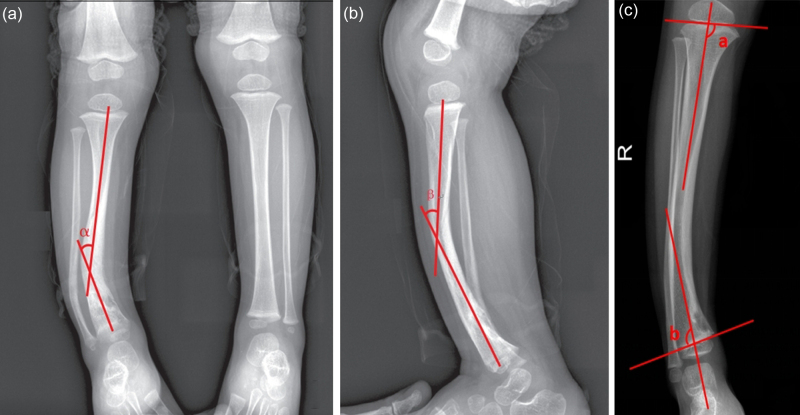

本研究的目的是探讨引导生长技术治疗儿童先天性胫骨前外侧弯曲(ALBT)的早期有效性。对2020年1月至2022年10月在两个中心接受“U”型钉引导生长技术治疗的18例ALBT患者进行回顾性分析。术前、取出植入物时或最后一次随访时采集双下肢、胫骨和腓骨的正侧位x线片。统计分析胫骨干骺端冠状角、矢状角、胫骨内侧近端解剖角(aMPTA)和胫骨外侧远端解剖角(alta)的变化,评价ALBT的矫正效果。所有患者平均随访23.36个月(14.53 ~ 37.2个月)。18例患者均表现出冠状面胫骨轴角的改善,平均矫正17.94°(范围:5.54°-33.52°)。14例患者矢状面胫骨轴角改善,平均矫正13.44°(范围:1.89°-32.6°)。治疗后aMPTA和alta水平均下降。随访期间,18例患者均未发生胫骨假关节。引导生长技术可以有效地改善ALBT,防止胫骨进一步的角度畸形,并可能延迟或预防胫骨假关节。此外,引导生长技术操作简单,微创,并发症少。

The aim of this study was to investigate the early effectiveness of guided growth techniques for managing congenital anterolateral bowing of the tibia (ALBT) in children. A retrospective analysis was performed involving 18 patients with ALBT treated with the 'U'-shaped staple-guided growth technique between January 2020 and October 2022 at two centres. Anteroposterior and lateral radiographs of both lower limbs and the tibia as well as the fibula were collected before surgery, at the time of implant removal, or at the last follow-up. Changes in the coronal tibial diaphyseal angulation, sagittal tibial diaphyseal angulation, anatomical medial proximal tibial angle (aMPTA) and anatomical lateral distal tibial angle (aLDTA) were statistically analysed to evaluate the correction effect of the ALBT. All patients were followed up for an average of 23.36 months (range: 14.53-37.2 months). All 18 patients demonstrated an improvement in the coronal plane tibial shaft angle, with an average correction of 17.94° (range: 5.54°-33.52°). Fourteen patients displayed an improvement in the sagittal plane tibial shaft angle, with an average correction of 13.44° (range: 1.89°-32.6°). Both the aMPTA and aLDTA levels decreased after treatment. No tibial pseudarthrosis occurred in any of the 18 patients during the follow-up. The guided growth technique is effective in improving the ALBT, preventing further angular deformities of the tibia, and may delay or prevent tibial pseudarthrosis. Moreover, the guided growth technique is simple to perform, minimally invasive and associated with few complications.